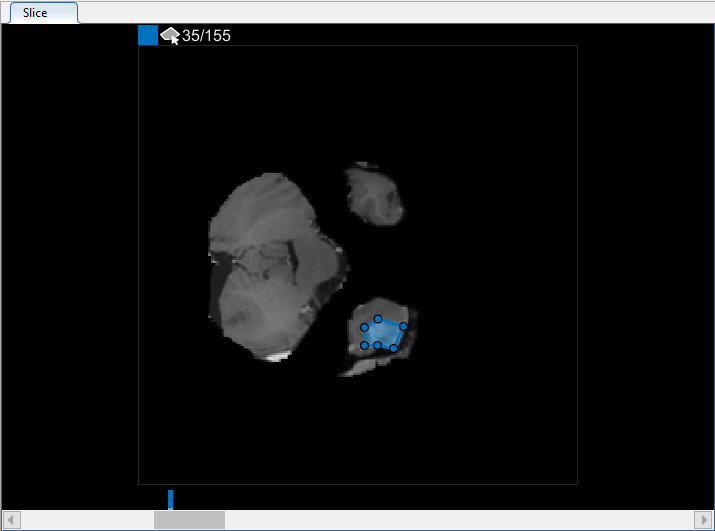

В панели Среза перейдите к срезу, где объект сначала появляется, срез 35, и чертите схему вокруг объекта. В данном примере используйте инструмент для рисования Многоугольника. Щелкните, чтобы создать вершину, затем переместите курсор и щелкните еще раз, чтобы создать вторую вершину прямой линией, соединяющей их. Продолжите этот процесс, чтобы создать связанную линию. Чтобы добавить дополнительные вершины после того, как вы закончите чертить, дважды кликните на ребре ROI.

Чтобы использовать интерполяцию, необходимо сначала вручную задать область на двух срезах. Вы уже задали область на первом срезе, где объект появляется, срез 35. Используйте тот же процесс, чтобы задать область на последнем срезе, где это появляется, срез 88. Приложение помещает две панели сверху ползунка, с помощью цвета, сопоставленного с меткой, чтобы указать на срезы с ROI.